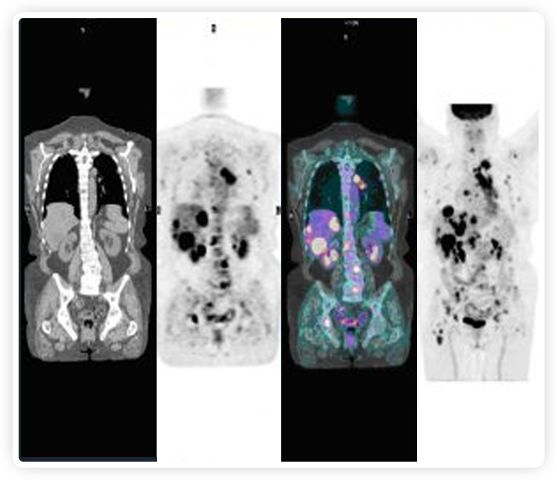

正電子發(fā)射斷層掃描(PET)是癌癥檢測(cè)中已建立的成像標(biāo)準(zhǔn),與其他成像方式相比,PET能提供高靈敏度和特異性的圖像。

到目前為止,放射腫瘤學(xué)中(使用的圖像主要是結(jié)構(gòu)性的,而PET圖像可以提供生物學(xué)信息。通過使用注射示蹤劑,例如18-FDG,PET可以描繪腫瘤的代謝活性,使其“點(diǎn)亮”。(FDG是用于可視化癌癥代謝的最廣泛使用的示蹤劑。與正常組織相比,腫瘤細(xì)胞保留更高水平的FDG。)不同的PET示蹤劑可以識(shí)別腫瘤的不同生物學(xué)特征,例如特定生物標(biāo)志物抗原(例如,PSMA)或甚至探測(cè)免疫系統(tǒng)本身(例如,PDL1表達(dá)或活化的T細(xì)胞)。